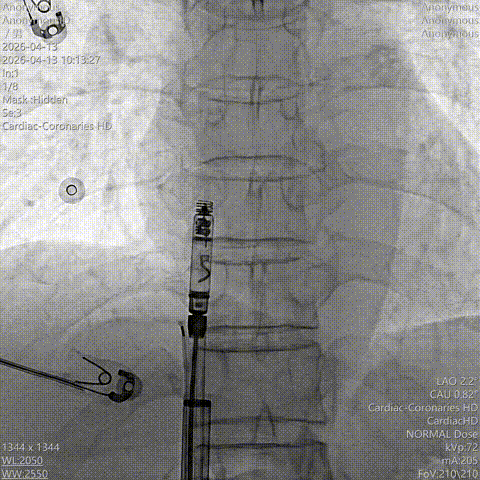

(3)调整角度到达右心耳基底部后,RAO 30°影像可判断右心耳深度,预判新型主动螺旋固定式无导线起搏器植入最佳位置造影,位置理想;LAO 30°造影明确朝向并贴靠右心耳基底部。

RAO造影

LAO造影